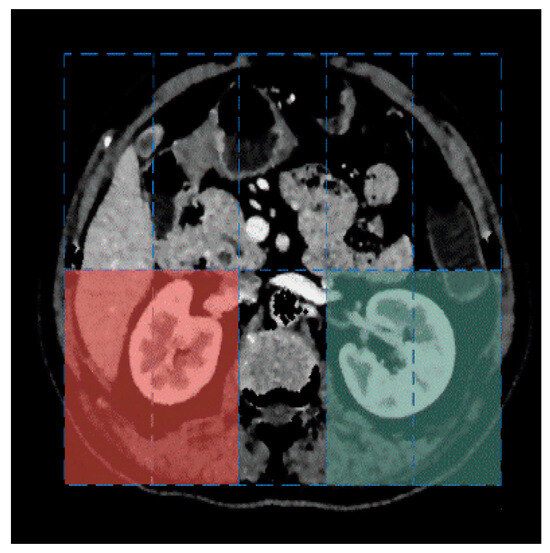

where c i is the centroid of the connection component i , and R l e f t and R r i g h t represent the expected anatomical locations of the centroids of the left and right kidneys, respectively. As shown in Figure 5, the blue rectangle indicates the minimum bounding box of the smallest convex polygon enclosing the spine and ribs. We divide this bounding box into two vertical halves and five horizontal sections. The region in the bottom-left of the bounding box is referred to as R l e f t , while the region in the bottom-right is referred to as R r i g h t . The spatial constraint R l o c a t i o n ( i ) helps filter out contours like the heart, while the circularity constraint R s h a p e ( f c i r c l e ( i ) ) helps filter out contours like the kidney and spleen.

Figure 5. The left kidney region R l e f t is indicated by the red color, and the right kidney region R r i g h t is indicated by the green color.